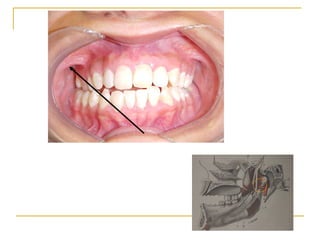

Bloqueo dentario inferior

TECNICAS DE ANESTESIA BLOQUEO DEL NERVIO INFERIOR  OTROS NOMBRES COMUNES Bloqueo mandibular NERVIOS ANESTESIADOS N. ALVEOLAR INFERIOR, UNA RAMA DE LA DIVISIÓN POSTERIOR DEL N. MANDIBULAR INCISIVO Y MENTONIANO (RAMAS TERMINALES DEL ALVEOLAR INFERIOR) LINGUAL

TECNICAS DE ANESTESIA AREAS ANESTESIADAS 1.- Dientes mandibulares  de la línea media. 2.- Cuerpo de la mandíbula , porción inferior de la rama. 3.- Mucoperiostio bucal, membrana mucosa anterior de la  primera molar ( nervio mentoniano). 4.- Dos tercios anteriores de la lengua y piso de la cavidad oral  (nervio lingual). 5.- Tejidos blandos de la lengua y periostio (nervio lingual).

TECNICAS DE ANESTESIA INDICACIONES Procedimientos en múltiples dientes mandibulares en un cuadrante. Cuando es requerida la anestesia del tejido blando bucal (anterior a la primera molar ). Cuando se requiere  anestesia del tejido lingual .

TECNICAS DE ANESTESIA CONTRAINDICACIONES Infecciones o inflamación aguda  del área de inyección. Los pacientes quienes pueden morder el labio o la lengua, o niños muy pequeños o discapacitados adultos o niños.

TECNICAS DE ANESTESIA VENTAJAS Una inyección provee un área amplia de anestesia (útil para cuadrante). DESVENTAJAS Área amplia de anestesia ( no es necesario para procedimientos localizados) Dosis inadecuada de anestesia ( 15% a 20%) La marca intraoral  no se considera real. Posible aspiración  ( 10% a 25%  muy alto de toda la técnica de inyección intraoral).

TECNICAS DE ANESTESIA Anestesia  lingual y labio inferior , fallida a muchos pacientes y posible daño en algunas personas. Posible anestesia donde el nervio alveolar inferior  se divide y canales mandibulares bífidos están presentes.